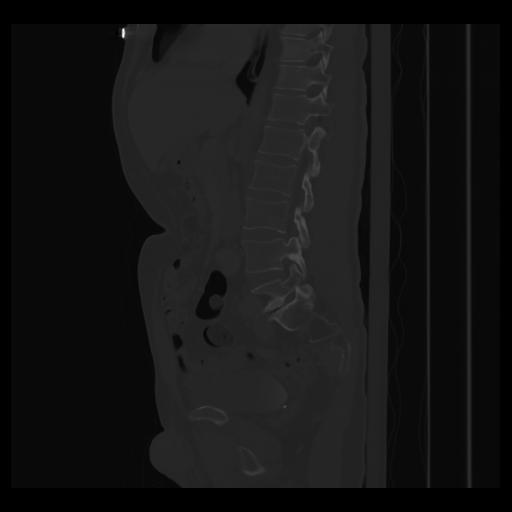

36 CUERPO,CE,Sagittal,3.000,CUERPO,Sagittal,